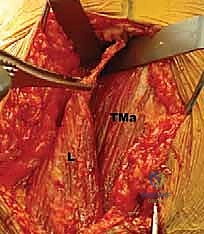

FIG 1 • A. Cadaveric dissection showing the interval between the teres major (TMa) and latissimus dorsi (L) tendons, with the radial nerve (R) deep to the latissimus and the axillary nerve (Ax) superior.

- Axillary Nerve: The axillary nerve runs superior to the latissimus dorsi tendon before exiting the quadrangular space. In neural rotation and adduction, the average distance between the nerve and the superior border of the tendon is 1.9 cm. Like the radial nerve, this distance increases with external rotation and abduction and decreases with internal rotation.